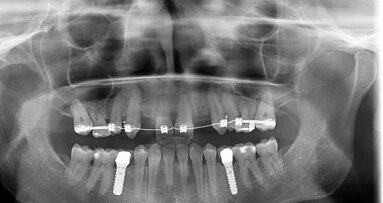

In 2018 werd patiënte naar de KvPA doorverwezen om te kijken of de esthetiek van met name het bovenfront verbeterd zou kunnen worden. Het betreft hier een ...